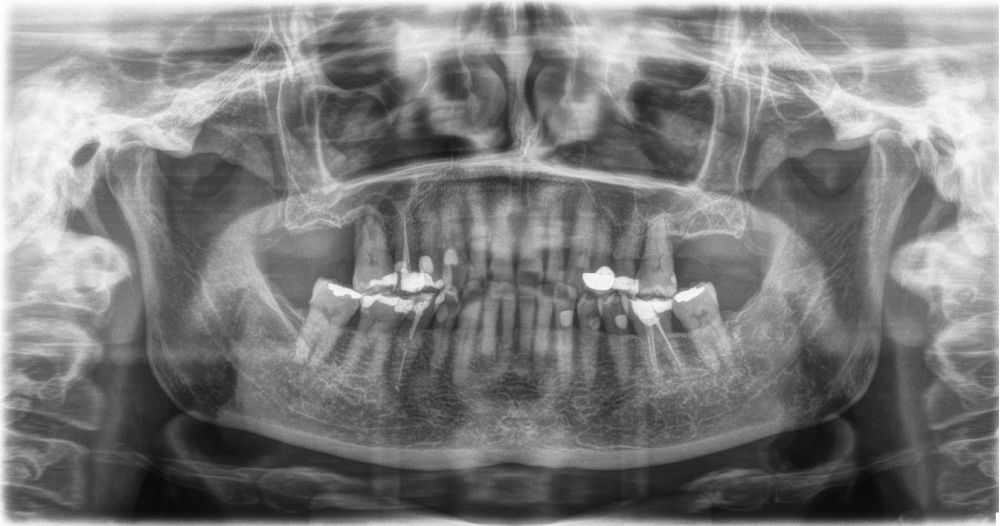

Introducción. El abordaje transcrestal del seno maxilar con y sin material de relleno como injerto es una técnica ampliamente extendida en nuestros días. Generalmente se combina con la utilización de implantes cortos y extracortos. En este trabajo, presentamos una serie de casos tratados con un protocolo unificado con un seguimiento de 10 años.

Material y método. Se ha llevado a cabo un estudio retrospectivo de pacientes tratados mediante implantes extracortos (5,5 y 6,5 mm de longitud) colocados mediante elevación transcrestal sin el uso de injerto. Como variables principales se han estudiado: la pérdida ósea crestal de los implantes y la ganancia en altura sobre el ápice. Como variable secundaria se ha estudiado la supervivencia de los implantes.

Resultados. Fueron reclutados 13 pacientes en los que se insertaron 30 implantes. Una vez insertados y cargados los implantes, la altura media final fue de 9,68 mm (+/- 2,66), lo que supone una ganancia promedio de 5 mm. A los 10 años, se observó una disminución media de la altura ósea ganada en los implantes en conjunto de 0, 29 mm (+/- 0,77). La media de la pérdida ósea mesial fue de 0,73 mm (+/- 0,75 mm) y la media de la pérdida ósea distal fue de 0,98 mm (+/- 1,2 mm). La supervivencia fue del 100%.

Introduction. The transcrestal approach to the maxillary sinus with and without filler material as graft is a widespread technique nowadays. It is usually combined with the use of short and extra-short implants. In this paper, we present a series of cases treated with a unified protocol with a 10-year follow-up.

Material and methods. A retrospective study of patients treated with extra-short implants (5.5 and 6.5 mm in length) placed by transcrestal elevation without the use of a graft was carried out. The main variables studied were: the crestal bone loss of the implants and the gain in height above the apex. Implant survival was studied as a secondary variable.

Results.Thirteen patients were recruited and 30 implants were inserted. Once the implants were inserted and loaded, the mean final height was 9.68 mm (+/- 2.66), which represents an average gain of 5 mm. At 10 years, there was a mean decrease in the overall bone height gain of the implants of 0.29 mm (+/- 0.77). The mean mesial bone loss was 0.73 mm (+/- 0.75 mm) and the mean distal bone loss was 0.98 mm (+/- 1.2 mm). Survival was 100%.